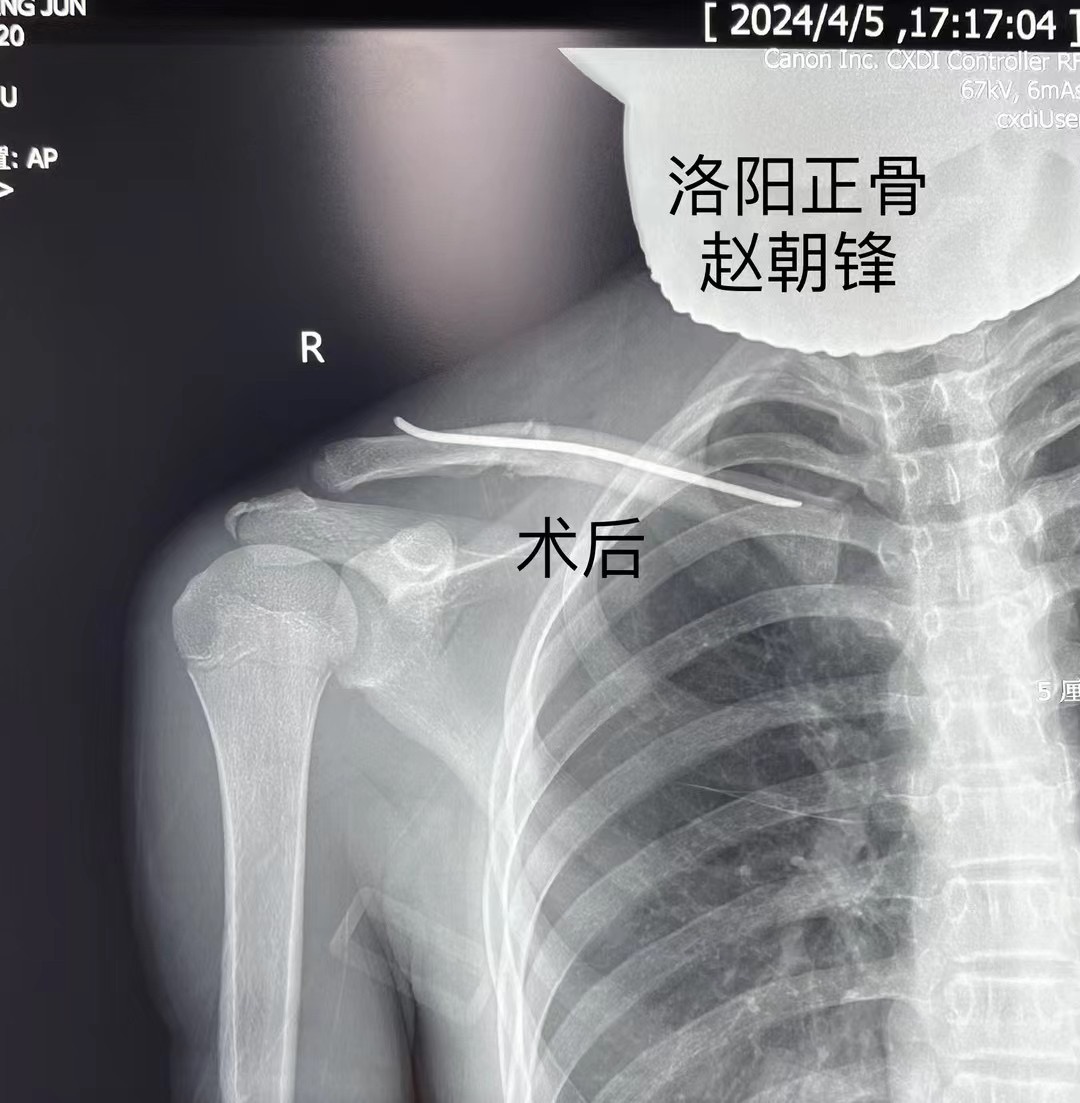

谢先生的孩子,小谢同学今年15岁,在跑着玩耍时摔倒,造成右肩部肿痛、活动受限,拍片显示右锁骨骨折,错位明显,辗转多家医院就医,均表示要开刀,放入钢板固定,但是小谢同学将来要报考军校,多年梦想,不想因为一朝骨折就放弃,于是慕名来到我院,找到手法正骨二科(微创正骨二科)主诊组长赵朝锋,经过制定详细的手术方案,主诊组长赵朝锋建议采用“手法复位、闭合穿针”治疗,这种方法具有创伤小、愈合快、功能恢复好、无皮肤切口瘢痕等诸多优点,在术后换药时,谢先生仔细观察了孩子的伤口:“没有切开皮肤,只在皮肤上留下了几个小眼,效果真好!”